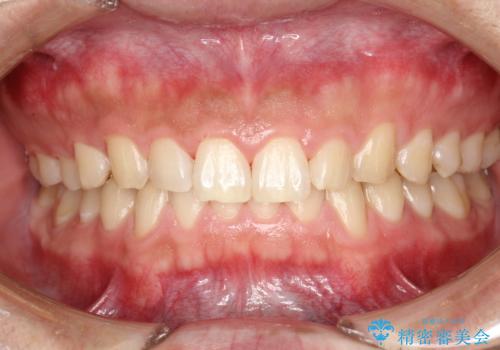

- 半年ぶりの来院で、全体的なチェックとクリーニング希望でした。PMTC(自費クリーニング)60分コースを行いました。

PMTCとは、プロフェッショナル(歯科衛生士)メカニカル(機械的)トゥース(歯)クリーニング(清掃)の略です。歯科医院にて、いろいろな機械・材料を使用し汚れを落とします。

磨き残しや、細菌は歯の表面がザラザラしている部分につきやすいです。そのためPMTCを定期的に繰り返すことで、歯の表面がツルツルの状態である期間が長くなるため、虫歯や歯周病予防につながります。